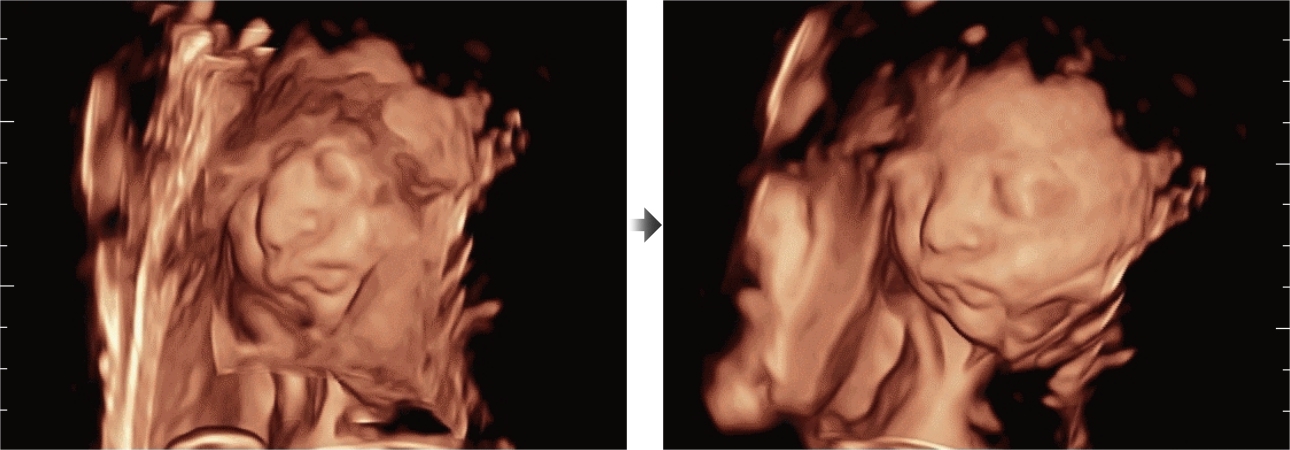

Обеспечивая качество изображения уровня премиум, Resona 7 также повышает клинические возможности исследования при помощи революционной системы V Flow, предназначенной для оценки гемодинамических показателей сосудов; обеспечивает интеллектуальное получение из 3D данных наиболее важных проекций для диагностики ЦНС плода. Сочетая в себе интуитивно понятное сенсорное управление с распознаванием жестов и все важные клинические характеристики, передовая система Resona 7 настоящая новая волна в сфере ультразвуковых инноваций.Благодаря перечисленным выше характеристикам, Resona 7 является доступным решением премиум-класса, которое удовлетворяет высоким требованиям клинической точности и эффективной диагностики в условиях современной перегруженной больничной среды.